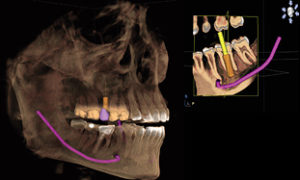

CTの導入により、今までは2次元のレントゲン写真しか撮影できませんでしたが、これからは3次元のCTデータによる診断が可能になります

インプラント治療においては補綴表示とインプラント計画の同時サポートで、新たなアプローチをもたらします。CERECでデザインされたクラウンとCT画像が融合され、一画面上に表示することができるソリューション。これにより、安全性が高くよりシンプルなプランニングが可能になります。3Dビューにより、患者さんへの治療計画の説明を画面を見せながらわかり易く行うことが可能になります